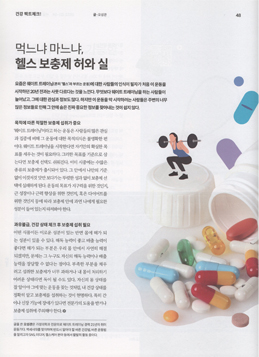

비만통증클리닉

비만통증클리닉

체형 진단 및 운동치료

- 비만통증클리닉

- 체형진단 및 운동치료